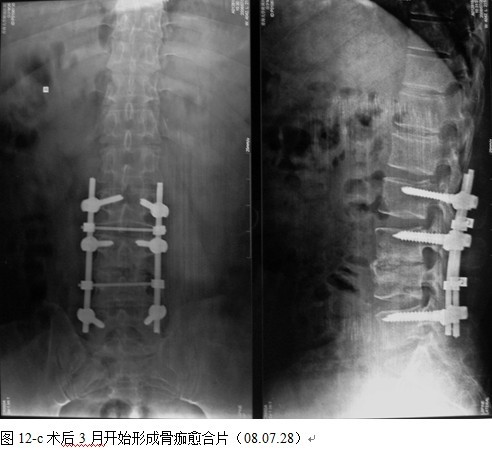

本组手术用时间3~4h , 平均3.5h 。术中出血300~500ml , 平均约350ml 。术后症状完全缓解,无神经功能障碍加重等并发症,1例营养差的老年患者伤口出现窦道,1例因肝功能差,术后未口服抗痨药,伤口出现窦道,经换药后二期愈合,其余病例伤口均一期愈合。马尾神经受损的患者术后基本恢复正常。术后一周后凸角平均 5.4°后凸畸形平均矫正90%以上, 最终后凸角平均8.3°,后凸角度平均丢失4.2°。随访3个月有87%(40/46)有骨痂形成,6个月91.3%(42/46)明显骨性愈合(见图),其余4例9-12个月内愈合,随访时间3-32个月,平均11个月,46例患者中2例在术后2个月和3个月时背部形成脓肿,换药后治愈。2例出院1月后并发结核性脑膜炎,治疗后好转。1例因椎弓根钉偏外,刺激神经根,5个月后从侧方脱出,疼痛加重,因前后路植骨完全愈合,取出后症状完全缓解。

4.1腰椎结核手术治疗中应用内固定的必要性和安全性:为了预防和矫正畸形,稳定脊柱,减少结核的复发率以及提高病变节段的融合率,让患者早期下床功能锻炼, 国内外学者将内固定用于脊柱结核的手术治疗中,取得了令人满意的效果[4、5、6、7、8、9、10]。通过本组病例观察,我们发现内固定的应用有着重要的作用,内固定不但可以预防,矫正后凸侧弯畸形,而且畸形的矫正率明显提高,未见畸形加重和矫正的明显丢失,还能使病变节段在术后即刻获得足够的稳定性, 为脊柱融合和结核病灶的静止提供一个良好的力学环境,促进了植骨融合,未见植骨块的吸收,移位和假关节的形成,术后结合支具治疗,大大缩短术后卧床时间,简化术后护理,利于患者全身情况的改善及后续康复治疗。